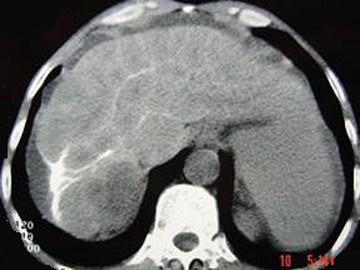

问题 男性,63岁,腹胀、双下肢水肿、乏力、食欲不振,影像所见如下图,最佳的诊断是 ( )

选项 A.酒精性肝硬化 B.血吸虫肝硬化 C.肝炎后肝硬化 D.局限性脂肪肝 E.原发性肝癌

答案 B